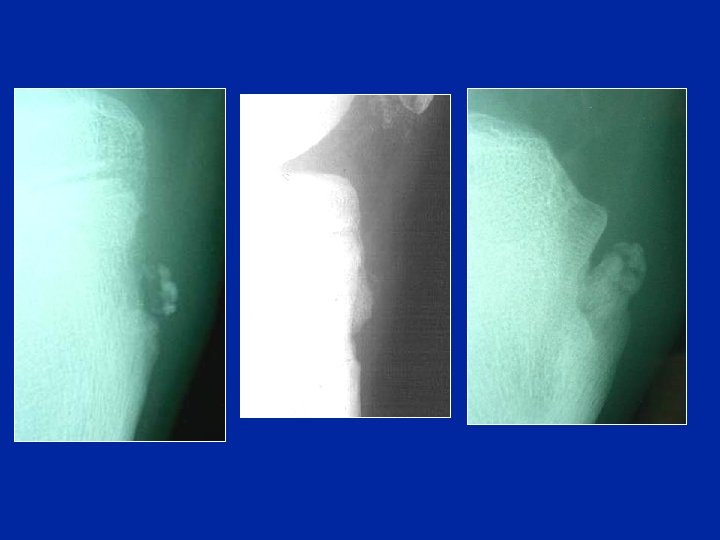

Osgood : radiologie • • Aspect “flou” du rostre épiphysaire Zone “rongée” de l’os épiphysaire sous-chondral Corps étrangers intratendineux Fragmentation de la zone d'insertion du tendon correspondant à des micro-arrachements ostéopériostés. • Déplacement antérieur du bec rostral • Rarement, arrachement complet • Œdème du tendon à l’IRM

Aspects radiologiques profil + rayons mous • • • Aspect “flou” du rostre épiphysaire Corps étrangers intratendineux Fragmentation de la zone d'insertion Déplacement antérieur du bec rostral Rarement, arrachement complet

Oedème du tendon à l’IRM